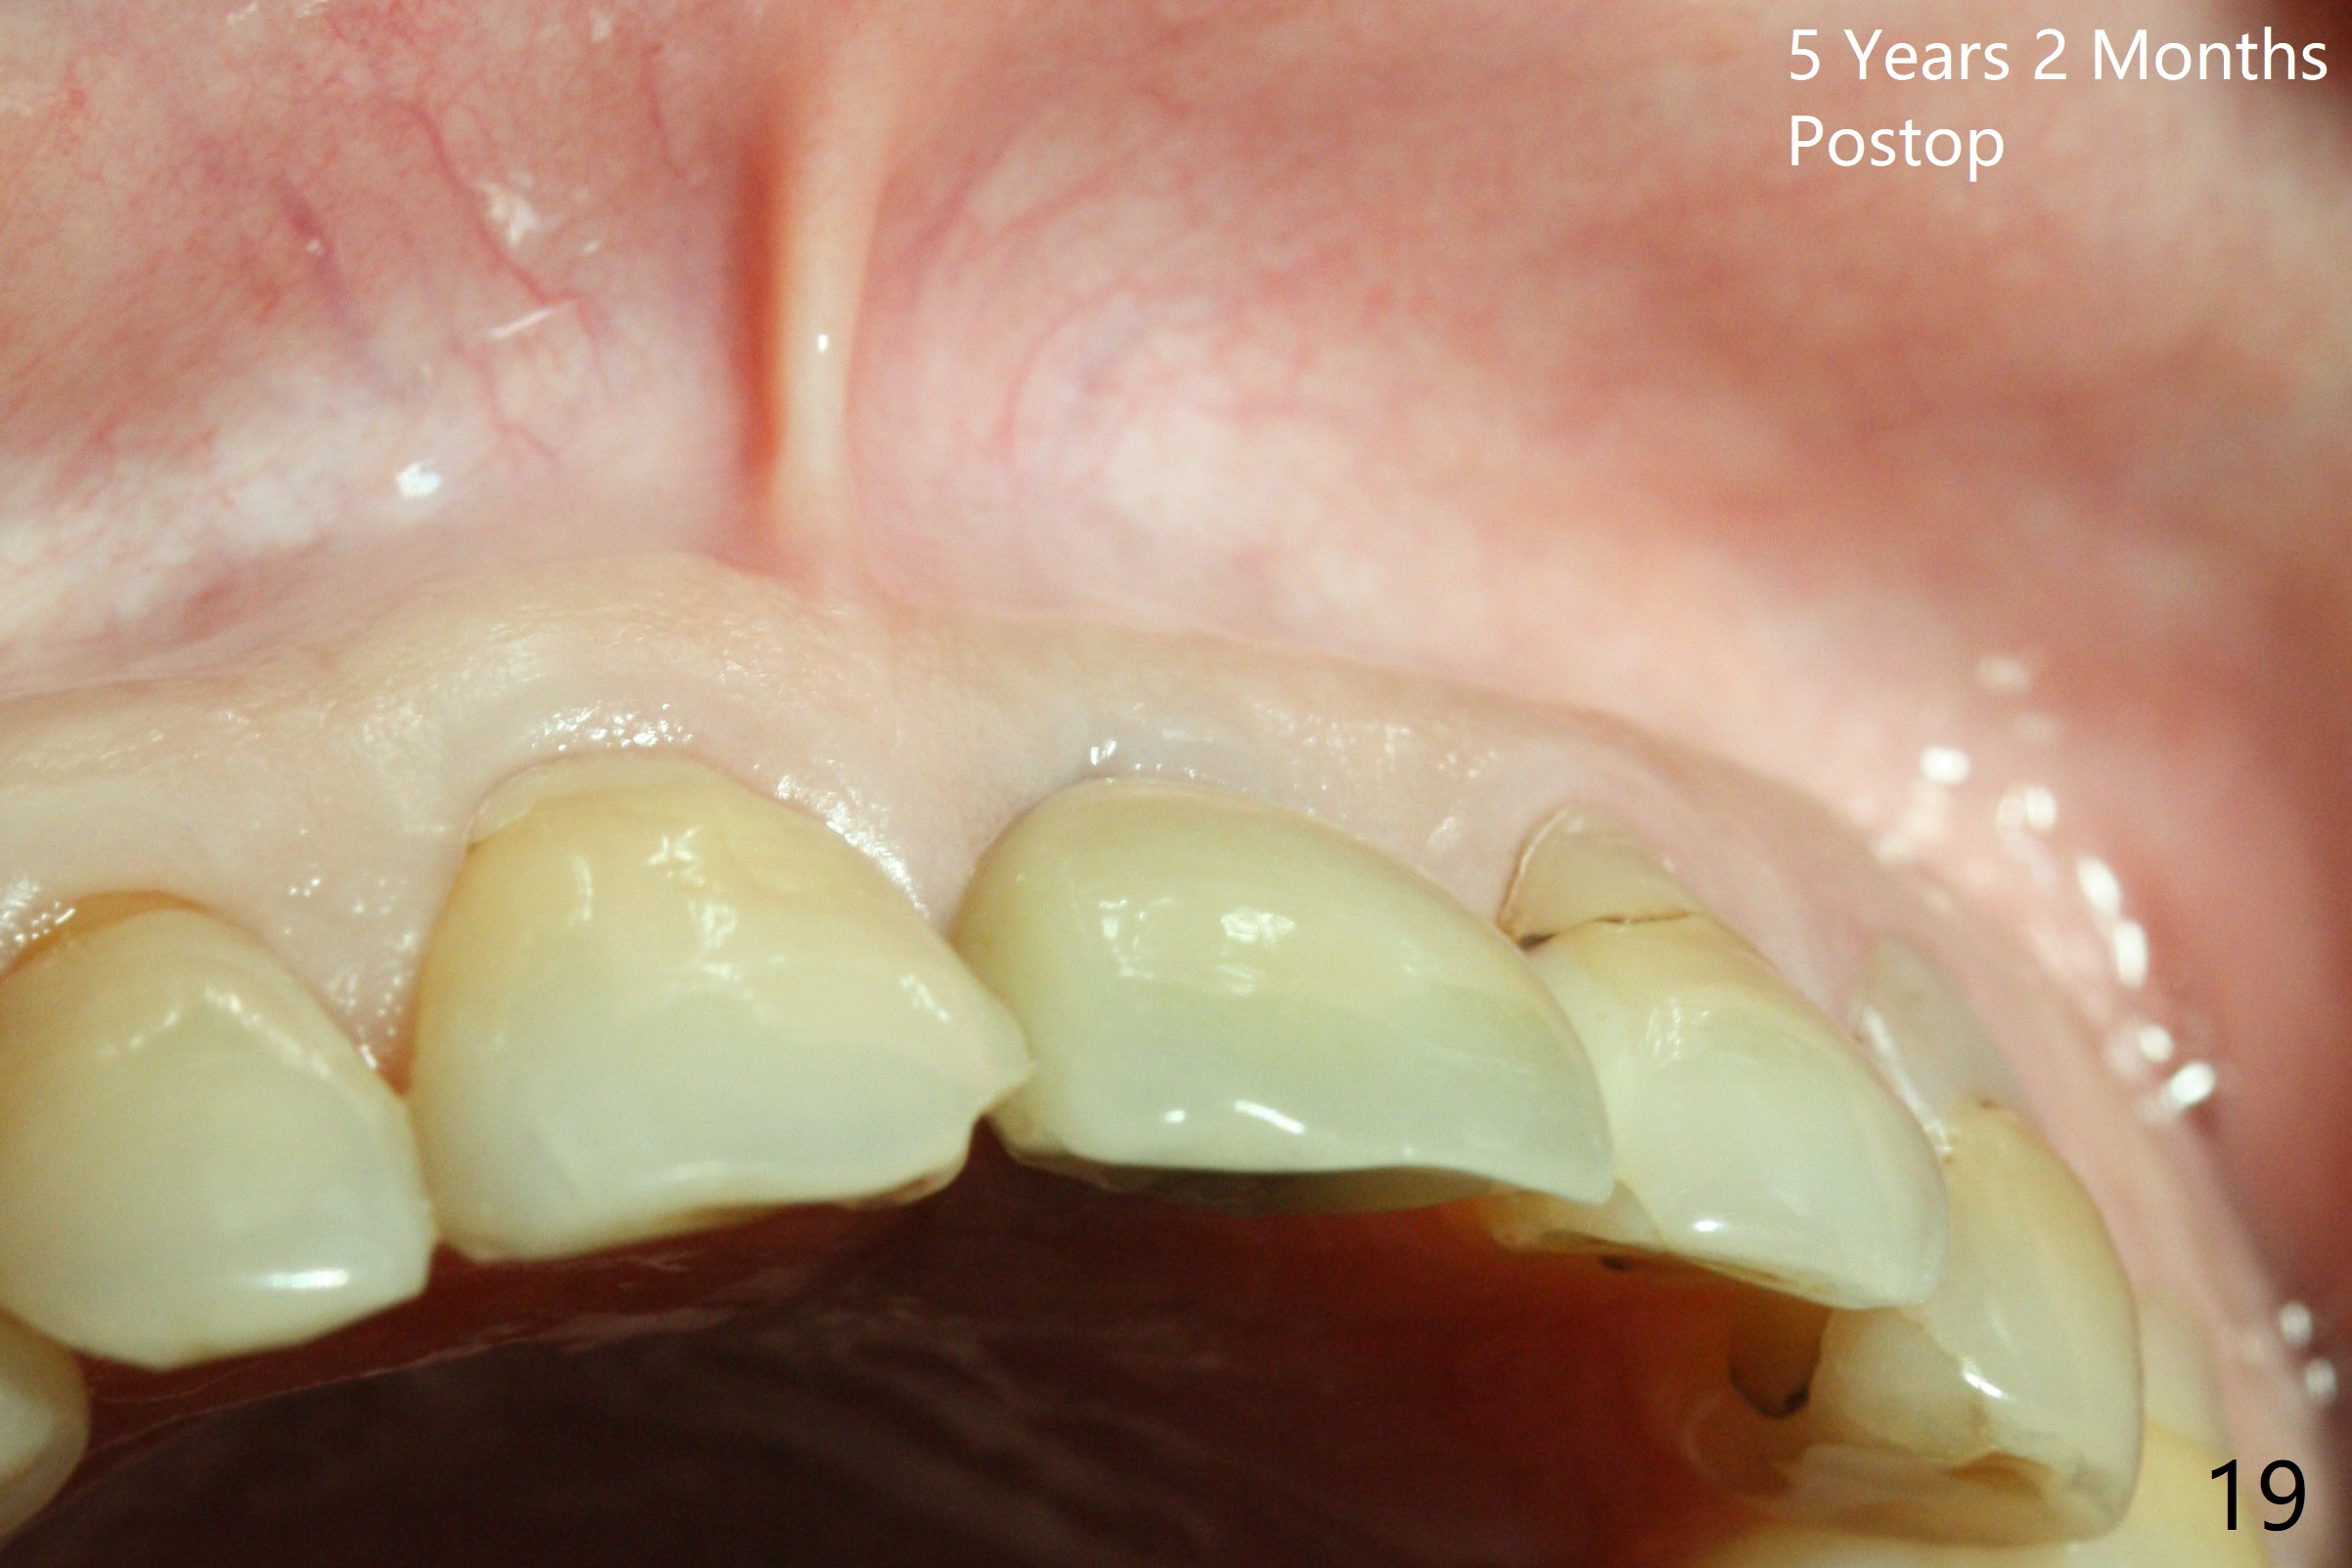

Postop tenderness lasts for two days. The palatal swelling is unnoticeable 7 days postop (Fig.9 *, as compared to A in Fig.8). The bone remains stable around the implant (Fig.10), while the gingiva healthy around the immediate provisional (Fig.11) 5 months postop. Due to insurance limit, the permanent restoration is delayed (16 months postop, Fig.12). The patient is satisfied with the function and appearance 3 years 8 months postop (21 months post cementation, Fig.13,14). PA is taken 4 years 1 month postop (2.5 years post cementation, Fig.15). The lamina dura forms from the most coronal threads (Fig.16). Although there is no bone loss around the implant (Fig.17), metal starts to show 5 years 2 months postop (Fig.18 ^), probably related to the buccal placement, too large the implant for the site or buccal plate atrophy (Fig.19).